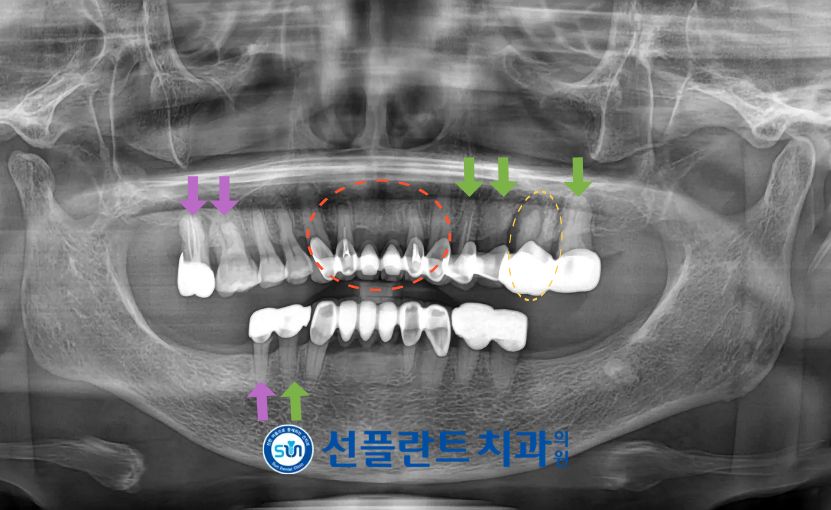

먼저 구강 내를

확인해 보았더니

불편감을 호소하셨던

왼쪽 위턱 첫 번째 큰 어금니(#26) 주변으로

고름이 나오고 있었으며

동요도 역시 심한 상태였는데요.

그리고 정밀 검사를 위해

파노라마 사진을 촬영해 보았더니

노란색 동그라미 표시의

위턱 왼쪽 첫 번째 큰 어금니(#26)가

뿌리 끝 염증으로 인한

골소실이 진행되고 있었으며

염증이 주변 뼈 잇몸으로 퍼지면서

고름이 배출되기 위해

누공이 형성되어 있는 상태로

안타깝지만 예후가 좋지 않아

발치가 불가피한 상황이었습니다.

위턱 왼쪽 두 번째 큰 어금니(#26)는

발치 후 뼈이식을 동반하여

임플란트 식립을 진행하기로 하였으며,

보라색 화살표 표시의 상태가 좋지 않은

위턱 오른쪽 큰 어금니(#16,17) 그리고

아래턱 오른쪽 두 번째 작은 어금니(#45)

역시 발치 후 상실된 부위와 함께

임플란트 수복을 진행하기로

치료 계획을 수립하였습니다.

이 외에도 치료가 필요한 부위엔

신경치료 + 크라운 수복을 계획했습니다.

ㅡ> 위턱 오른쪽 송곳니(#13)부터

왼쪽 송곳니(#23)까지

ㅡ> 초록색 화살표 표시의

위턱 왼쪽 작은 어금니(#24,25),

두 번째 큰 어금니(#27) 그리고

아래턱 오른쪽 첫 번째 작은 어금니(#44)